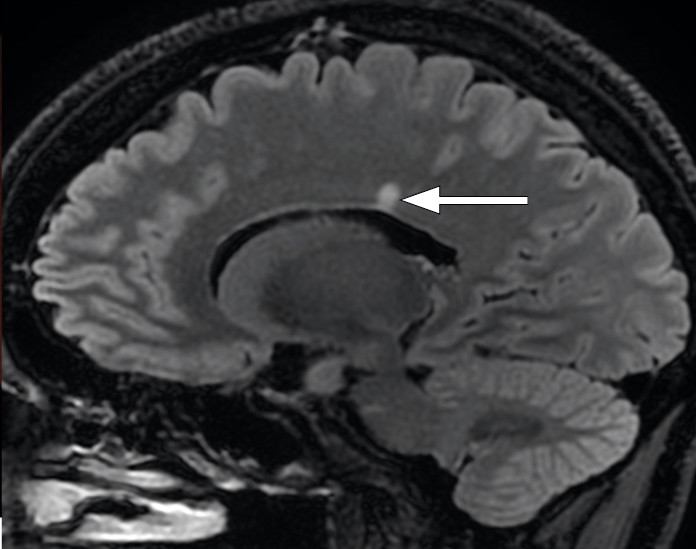

MR caput og orbita med kontrast viste normal fremstilling av begge synsnervene og ingen retrobulbær patologi. Intracerebralt ble det påvist en periventrikulær høysignalforandring med demyeliniserende karakteristika (figur 3). Ytterligere små, uspesifikke, punktformede høysignalforandringer ble fremstilt frontalt og parietalt på høyre side (figur 3). Ingen av lesjonene ladet kontrast som tegn på aktiv betennelse.

MR-funn av en periventrikulær høysignalforandring ga mistanke om demyeliniserende sykdom. Her så man imidlertid ikke betennelsesforandringer i synsnerven som forventet ved demyeliniserende optikusnevritt. Et infiltrat ved papillekanten og celler i glasslegemet (vitritt) kunne likne en okulær toksoplasmainfeksjon (2). MR ga imidlertid ikke holdepunkter for toksoplasmainfeksjon i sentralnervesystemet, som typisk kjennetegnes av multiple lesjoner med kontrastladning og perifokalt ødem (4). Vi mistenkte derfor at pasienten hadde to avhengige tilstander: en okulær toksoplasmainfeksjon, som forklarte symptomene, og i tillegg en subklinisk demyeliniserende sykdom.